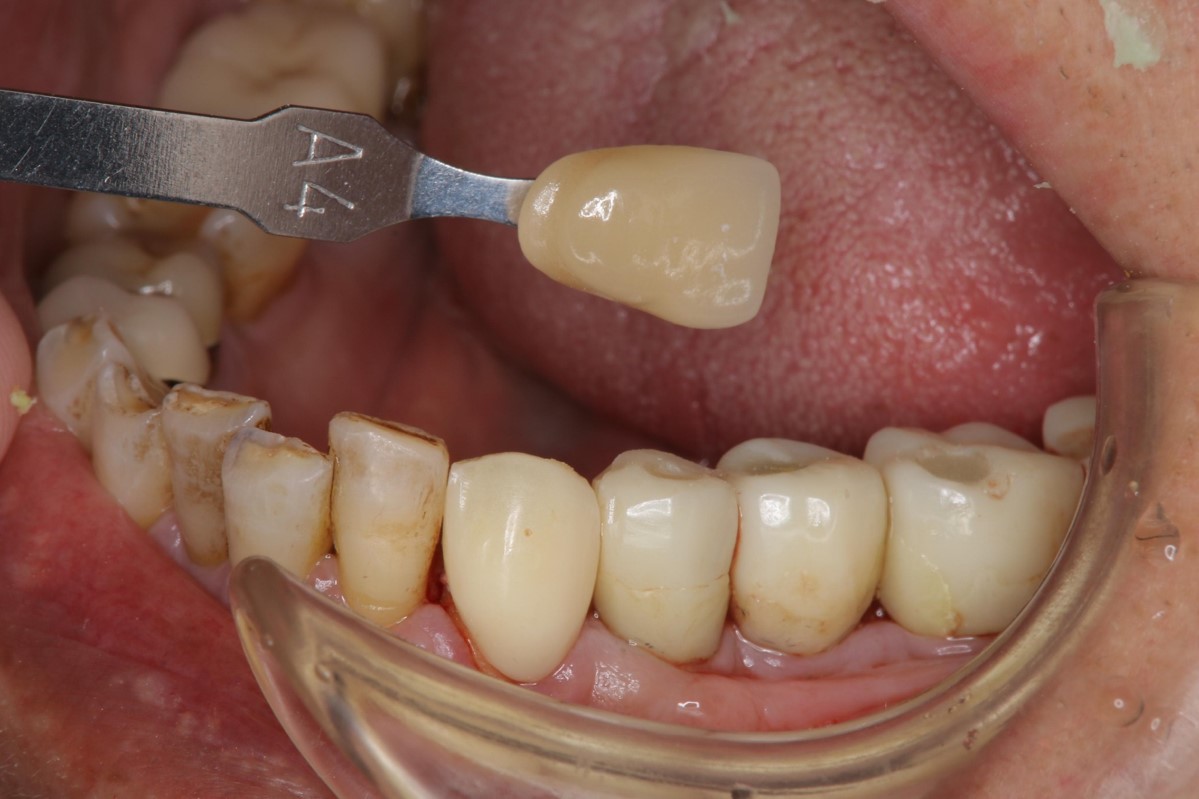

照相比色,這是我沒想到的,不然只有一顆牙齒顏色特別突兀,一看就知道會是假的,果然醫生還是很貼心的照顧到患者門面!

照相比色